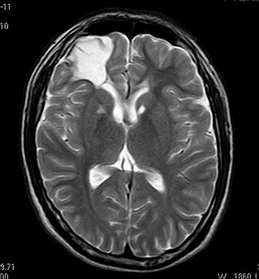

之后,钟先生来到广东三九脑科医院,头部MRI提示:右侧额叶软化灶形成并胶质增生;双侧基底节区小软化灶、胼胝体异常信号影,考虑陈旧轴索损伤可能;幕上弥漫性脑皮质萎缩。癫痫内科医生建议其手术治疗,但因经济条件等原因,钟先生继续服药治疗了几年。

最近1个月以来,钟先生的发作变得频繁,1个月发作2次。他来到神经外六科进一步检查,视频脑电图显示:重度异常脑电图;右侧颞区见少量中高波幅棘-慢波发放。脑磁图提示:右额区见稍多棘波发放。颅脑MR提示:右侧额叶软化灶形成并胶质增生;双侧基底节区小软化灶、胼胝体异常信号影,考虑陈旧轴索损伤可能;幕上弥漫性脑皮质萎缩。

术前MR